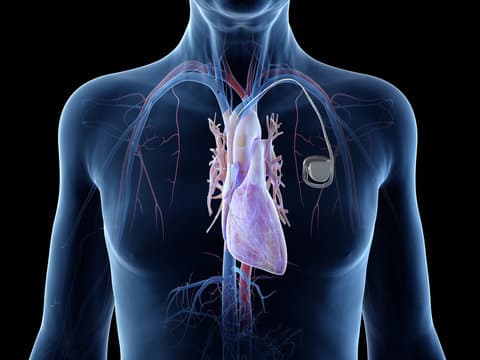

The pacemaker consists of two main components: a pulse generator and one or more leads (wires). The pulse generator is a small, battery-powered unit that produces electrical impulses. It is typically implanted under the skin, just below the collarbone. The leads are thin, flexible wires that extend from the pulse generator to the heart. These leads are threaded through blood vessels and attached to the heart muscle. They transmit the electrical impulses from the pulse generator to the heart, stimulating it to contract at a regular rate.

Modern pacemakers are sophisticated devices that can be programmed to meet the specific needs of each patient. They come in various types, including single-chamber, dual-chamber, and biventricular pacemakers. Single-chamber pacemakers have one lead that is usually placed in the right ventricle, while dual-chamber pacemakers have two leads placed in the right atrium and right ventricle, allowing for coordinated pacing of both chambers. Biventricular pacemakers, also known as cardiac resynchronization therapy (CRT) devices, have three leads placed in the right atrium, right ventricle, and left ventricle, and are used to improve the heart's efficiency in patients with heart failure.